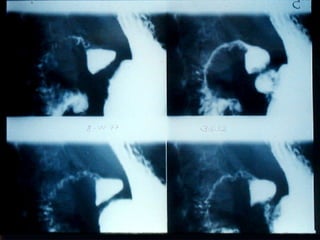

SEGD PATOLOGÍA ESOFÁGICA AFECCIONES DIVERSAS: Hernia de Hiato Divertículos Desgarro de Mallory Weiss y rotura esofágica

SEGD PATOLOGÍA ESOFÁGICAAFECCIONES DIVERSAS: Hernia de Hiato Divertículos Desgarro de Mallory Weiss y rotura esofágica